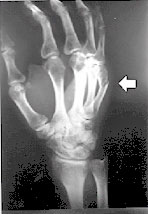

and in constant fear of his life. I am in possession of original

x-rays of his fractured hand, after one such beating took place, and

his hand was deliberately broken as a warning.